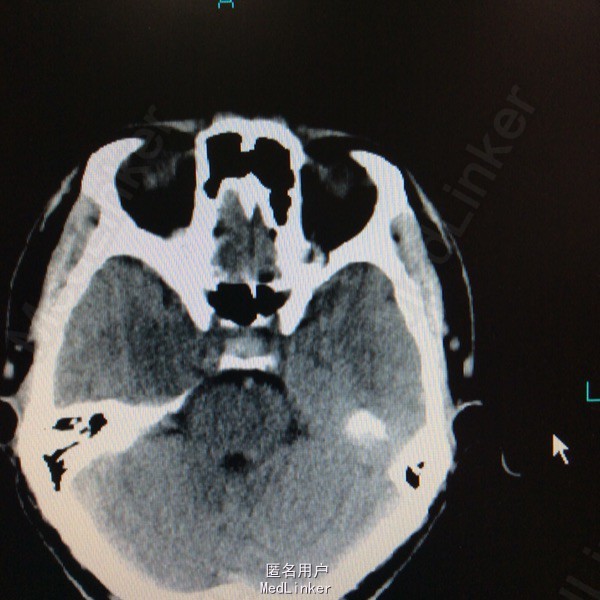

查体未见明显阳性体征,发育正常 头颅CT提示鞍区少量出血 MRI增强提示鞍区占位病变,大小约0.8*1.5cm 考虑垂体瘤卒中

术前诊断:垂体瘤 择期行经蝶入路垂体瘤切除术 术后病理提示垂体腺瘤